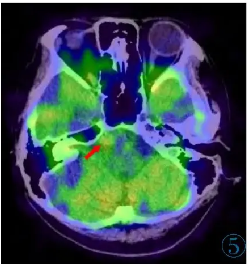

颅脑MRI示鞍上池、环池、侧裂池等区域的软脑膜呈弥漫性增厚、强化(图1),其中最大的结节凸向右侧桥脑前池,大小约11 mm×8 mm,呈宽基底与邻近脑膜相连,T1WI及T2WI呈等信号,增强扫描轻度强化,DWI未见弥散受限,PET-CT示该结节与脑膜病灶代谢轻度增高(图2~5)。脑室系统广泛扩张。左肺下叶外基底段可见数个实性小结节,边界清,直径约1~3 mm,代谢未见异常。

图5 PET-CT示该结节与脑膜病灶代谢轻度增高(红色箭头)。